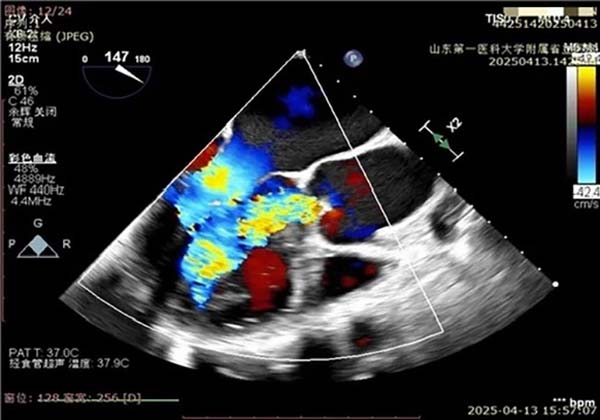

随后,团队迅速转换至TAVR程序。王安彪与朱梅配合,将瓣膜装载并引导至主动脉根部,通过TEE确认瓣环定位无误后,平稳释放瓣膜。超声即时显示人工瓣架固定牢靠,瓣叶开启顺畅,瓣周无间隙回声;多普勒测得瓣区最高流速225 cm/s,圧差20 mmHg,提示置换效果优异。

主动脉瓣植入,主动脉瓣返流明显改善